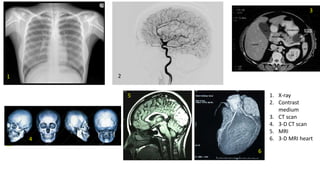

Starting in late 19th century several radiological

and nonradiological imaging techniques to

diagnose illness have been developed

Radiological

• Conventional x-ray

• Contrast media x-rays

• Cinematographic x-rays

• CT scans

Nonradiological

• MR scans

• Functional MR scans

• PET scans

• Ultrasound

1. X-ray

2. Contrast

medium

3. CT scan

4. 3-D CT scan

5. MRI

6. 3-D MRI heart